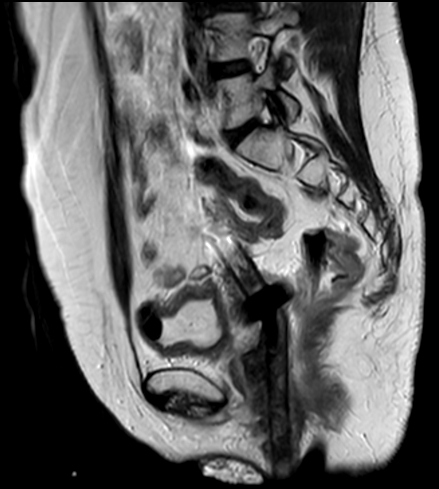

Patient with cervical cancer referred for MR-guided brachytherapy. MR imaging on Ingenia 1.5T with tandem-ring applicator in place for brachytherapy planning.

Sagittal 2D T2w TSE